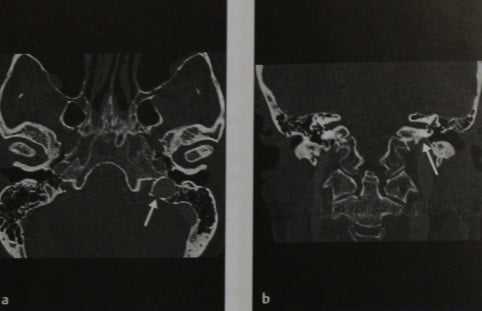

- Округлая структура с кортикальным краем в задней каменистой кости.

- Округлое, отчетливое гиперконтрастное образование в задней каменистой кости

- Подтверждение наличия высокого расположения яремной луковицы по данным МРВ.